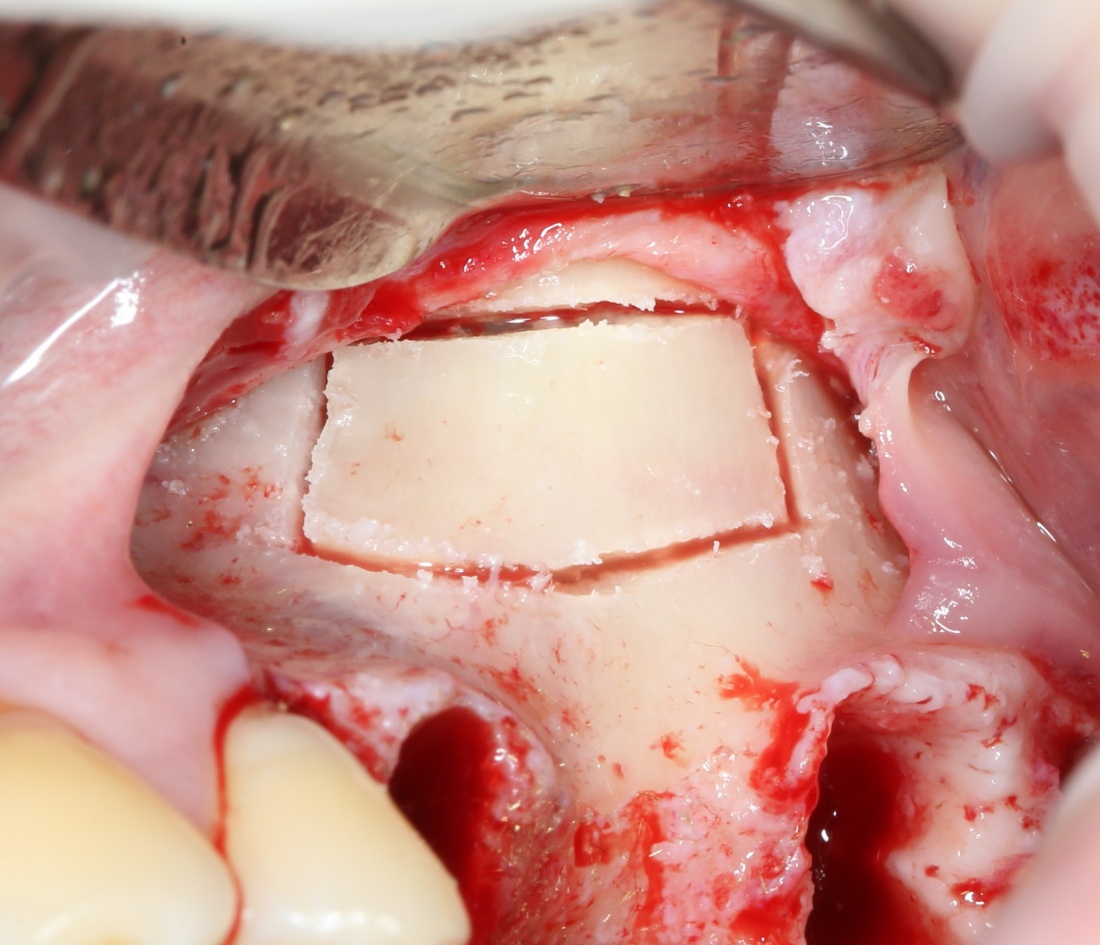

Синуслифтинг: что делать при перфорации слизистой оболочки гайморовой пазухи?